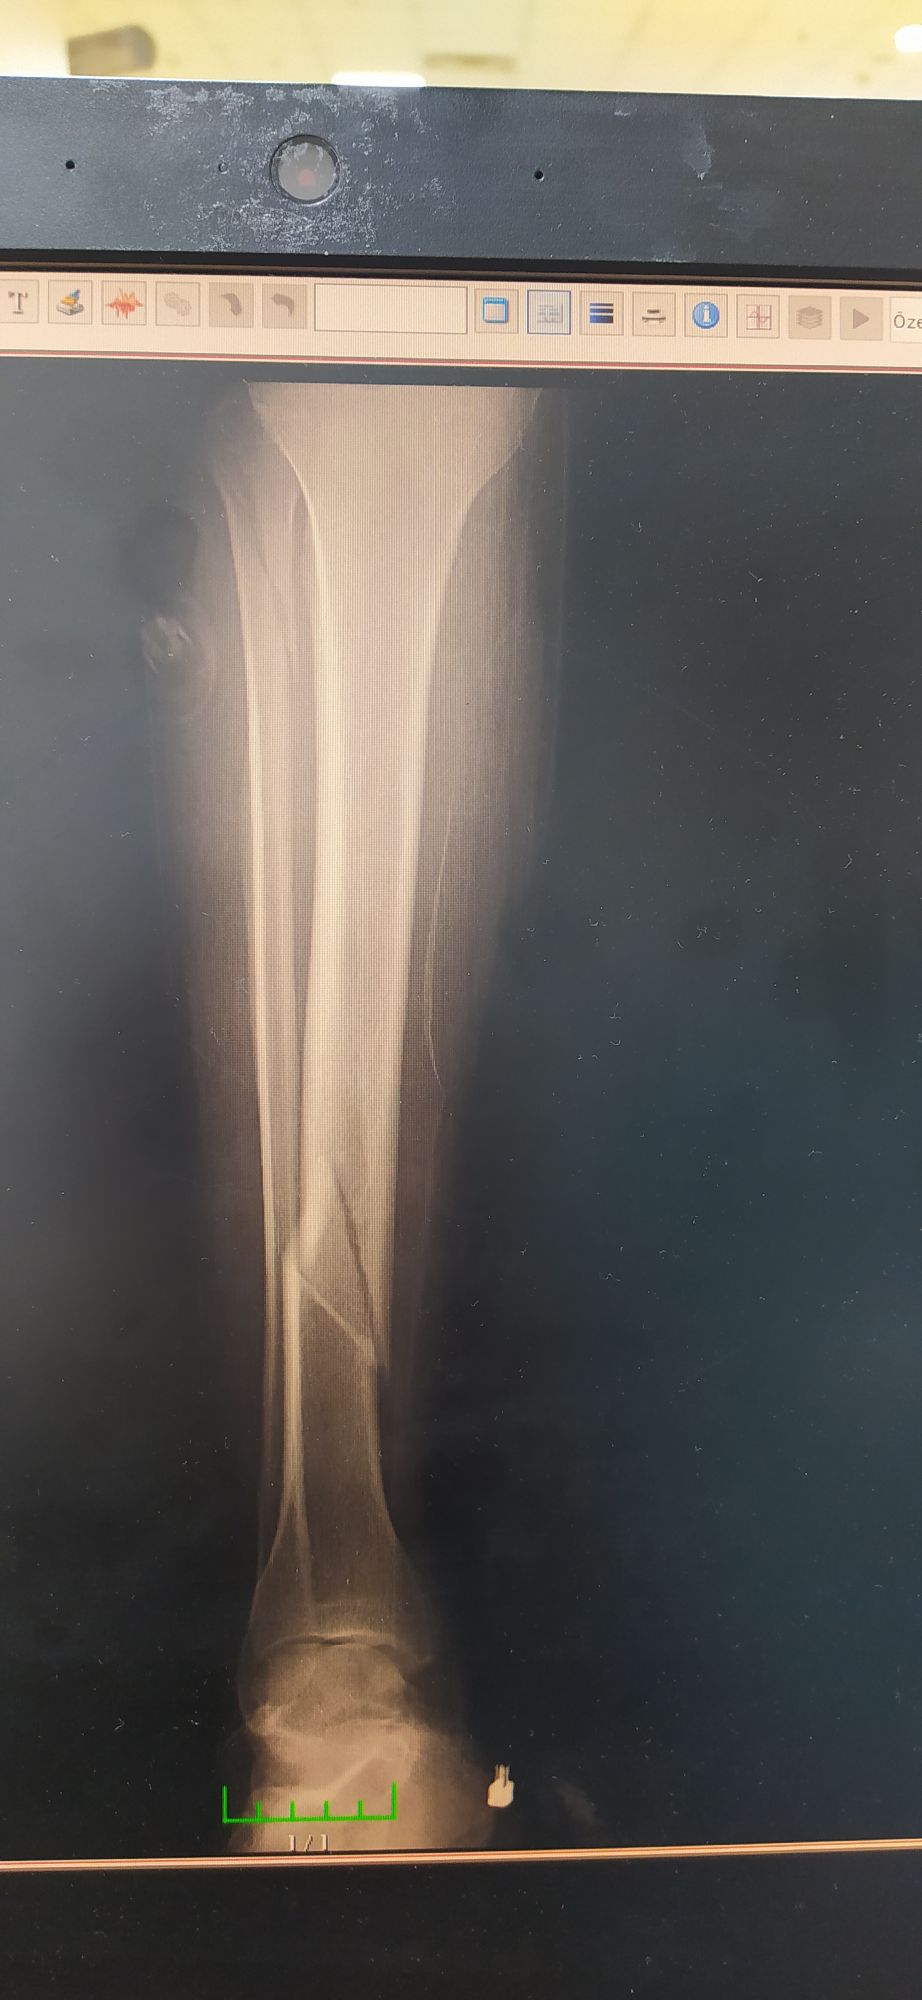

Post-football fracture

Fractures

Tibia

Fibula